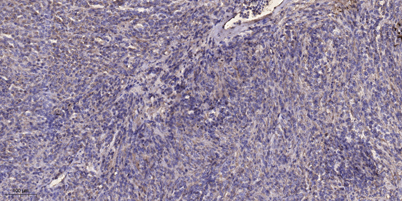

IHC

Recomended Dilution IHC-p 1:50-300